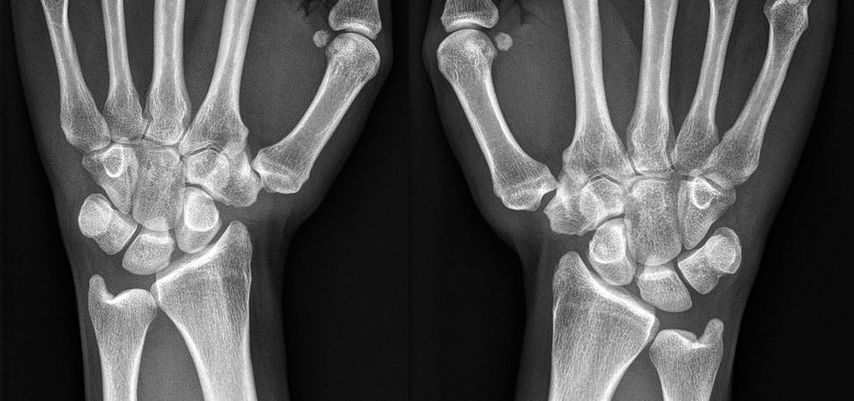

Abb. 1: Handgelenksröntgen einer 16-jährigen Patientin mit schmerzhafter CMC1-Instabilität rechts und deutlicher Trapeziumhypoplasie beidseits

Klinisch bemerkbar machen sich Instabilitäten durch Schmerzen, Bewegungseinschränkungen, Subluxationen, Schwellung in der Thenarregion8 und Kraftverlust. Vor allem beim kräftigen Spitzgriff zwischen Daumen und Zeigefinger kommt es dabei zu einer Translation der Basis des ersten Metacarpale nach dorsoradial. Geprüft wird die Stabilität des CMC1-Gelenkes, indem der Untersucher den Carpus mit einer Hand fixiert und mit der anderen das Metacarpale 1 im Schaftbereich umfasst. Anschließend wird versucht, den Daumen nach radial zu schieben, wobei es hier bei Instabilitäten des Gelenkes zu einer Translation über Schaftbreite kommen kann.11 Dokumentiert werden kann diese Translation auf Röntgenstressaufnahmen.